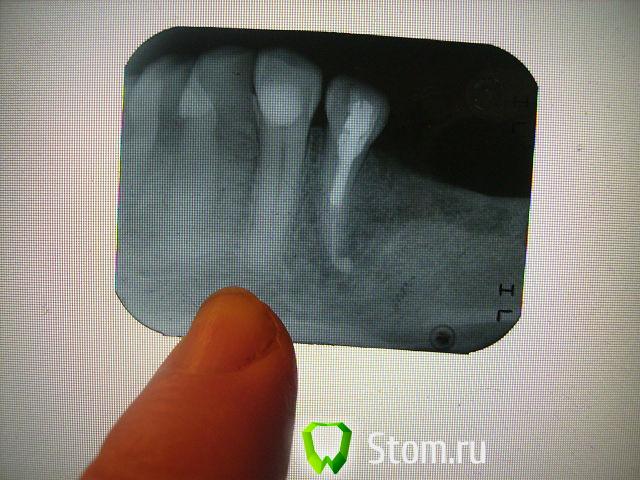

болящая Опубликовано 3 января, 2012 Поделиться Опубликовано 3 января, 2012 Уважаемые доктора! Перелечивала леченый 10 лет назад резорцин-формалиновый зуб (37).После перелечивания все дни боль при накусывании и ноющая самопроизвольная (10 дней) .Через 10 дней от перелечивания-свищ со щечной стороны с гнойным отделяемым ,боль ушла.Все дни обращалась к лечащему врачу. Ответ - все хорошо, на снимке каналы запломбированы отлично,а свищ-это реакция на перелечивание.То же сказал ортопед и закрепил мост на временный цемент (мост МК).Так ли хорошо на снимке с каналами,через неделю ставить мост на постоянный цемент, МК вещь не дешевая, что бы ее потом ломать. В настоящее время свищ закрылся, зуб не болит. Заранее спасибо за ответы. Ссылка на комментарий

DokDent Опубликовано 3 января, 2012 Поделиться Опубликовано 3 января, 2012 Уважаемые доктора! Перелечивала леченый 10 лет назад резорцин-формалиновый зуб (37).После перелечивания все дни боль при накусывании и ноющая самопроизвольная (10 дней) .Через 10 дней от перелечивания-свищ со щечной стороны с гнойным отделяемым ,боль ушла.Все дни обращалась к лечащему врачу. Ответ - все хорошо, на снимке каналы запломбированы отлично,а свищ-это реакция на перелечивание.То же сказал ортопед и закрепил мост на временный цемент (мост МК).Так ли хорошо на снимке с каналами,через неделю ставить мост на постоянный цемент, МК вещь не дешевая, что бы ее потом ломать. В настоящее время свищ закрылся, зуб не болит. Заранее спасибо за ответы. Я ничего хорошего не вижу.Свищ может открыться снова при обострении процесса. Ссылка на комментарий

DokDent Опубликовано 3 января, 2012 Поделиться Опубликовано 3 января, 2012 Спасибо за быстрый ответ! А можно поконкретней-что не так? Предположения любознательного рентгенолога,что есть еще один канал,который не пройден ни10 лет назад,ни сейчас.Неоднократные ответы доктора-все отлично,ничего болеть не может.Больше всего вводит в сомнение фраза-формирование свища при перелечивании каналов- благоприятный исход,свищ закроется и все будет хорошо! Каналы должны быть хорошо расширены,промыты и запломбированы на всём протяжении.На Ваших снимках этого нет.Если они плохо расширены,следовательно недомыты и незапломбированы как надо.Обострение периодонтита при перелечивании возможно,но если лечение проведено правильно-всё проходит,а если нет-может периодически повторяться. Ссылка на комментарий

juli63 Опубликовано 3 января, 2012 Поделиться Опубликовано 3 января, 2012 обращалась к лечащему врачу. Ответ - все хорошо, на снимке каналы запломбированы отлично,а свищ-это реакция на перелечивание.То же сказал ортопед и закрепил мост Мама дорогая....ужас.... судя по этому снимку, я осмелюсь предположить, что вам мост тут ставить нельзя! укажите номера зубов, которые являются его опорой(на которые коронки зафиксируют). Ссылка на комментарий